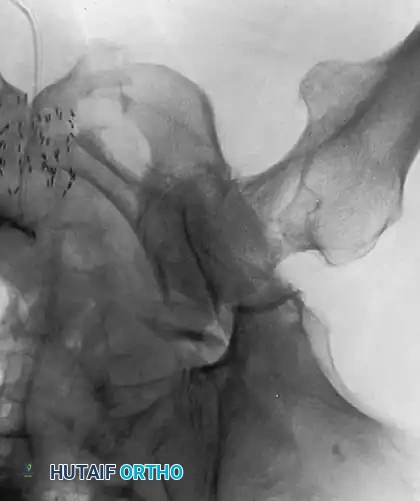

PROTRUSIO ACETABULI

Intrapelvic protrusio acetabuli is defined radiographically by the medial migration of the femoral head beyond the ilioischial (Kohler) line.

1. Primary Protrusio (Arthrokatadysis / Otto Pelvis): Typically bilateral, occurs in younger females, and leads to severe restriction of motion at an early age.

2. Secondary Protrusio: Results from conditions such as rheumatoid arthritis, ankylosing spondylitis, Paget disease, Marfan syndrome, osteomalacia, trauma (central fracture-dislocation), or migration of a previous endoprosthesis.

Fig. 7-74 Primary protrusio acetabuli. Otto pelvis in 52-year-old woman. Femoral head has migrated medial to ilioischial (Kohler) line. Hip motion is severely limited.

Principles of Reconstruction

The surgical management of protrusio acetabuli is technically demanding and relies on three non-negotiable biomechanical principles:

1. Restoration of the Anatomic Hip Center: The hip center of rotation must be lateralized and brought inferiorly to its true anatomic position to restore abductor mechanics and minimize joint reactive forces.

2. Peripheral Rim Fixation: The implant must be supported by the intact, structurally sound peripheral rim of the acetabulum, bypassing the deficient medial wall.

3. Medial Wall Reconstruction: Cavitary and segmental defects of the medial wall must be reconstituted, typically utilizing impaction bone grafting (autograft from the resected femoral head or allograft).